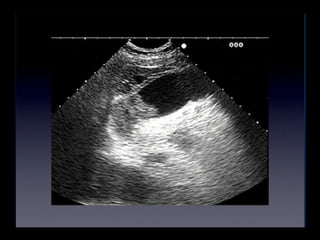

Colelitiasis

• Caracteristicas ecograficas

• Estructuras ecogénicas dentro de la luz

vesicular libre de ecos

• Sombra acustica con margenes “limpios”

• Dependencia gravitacional

• Son usualmente moviles